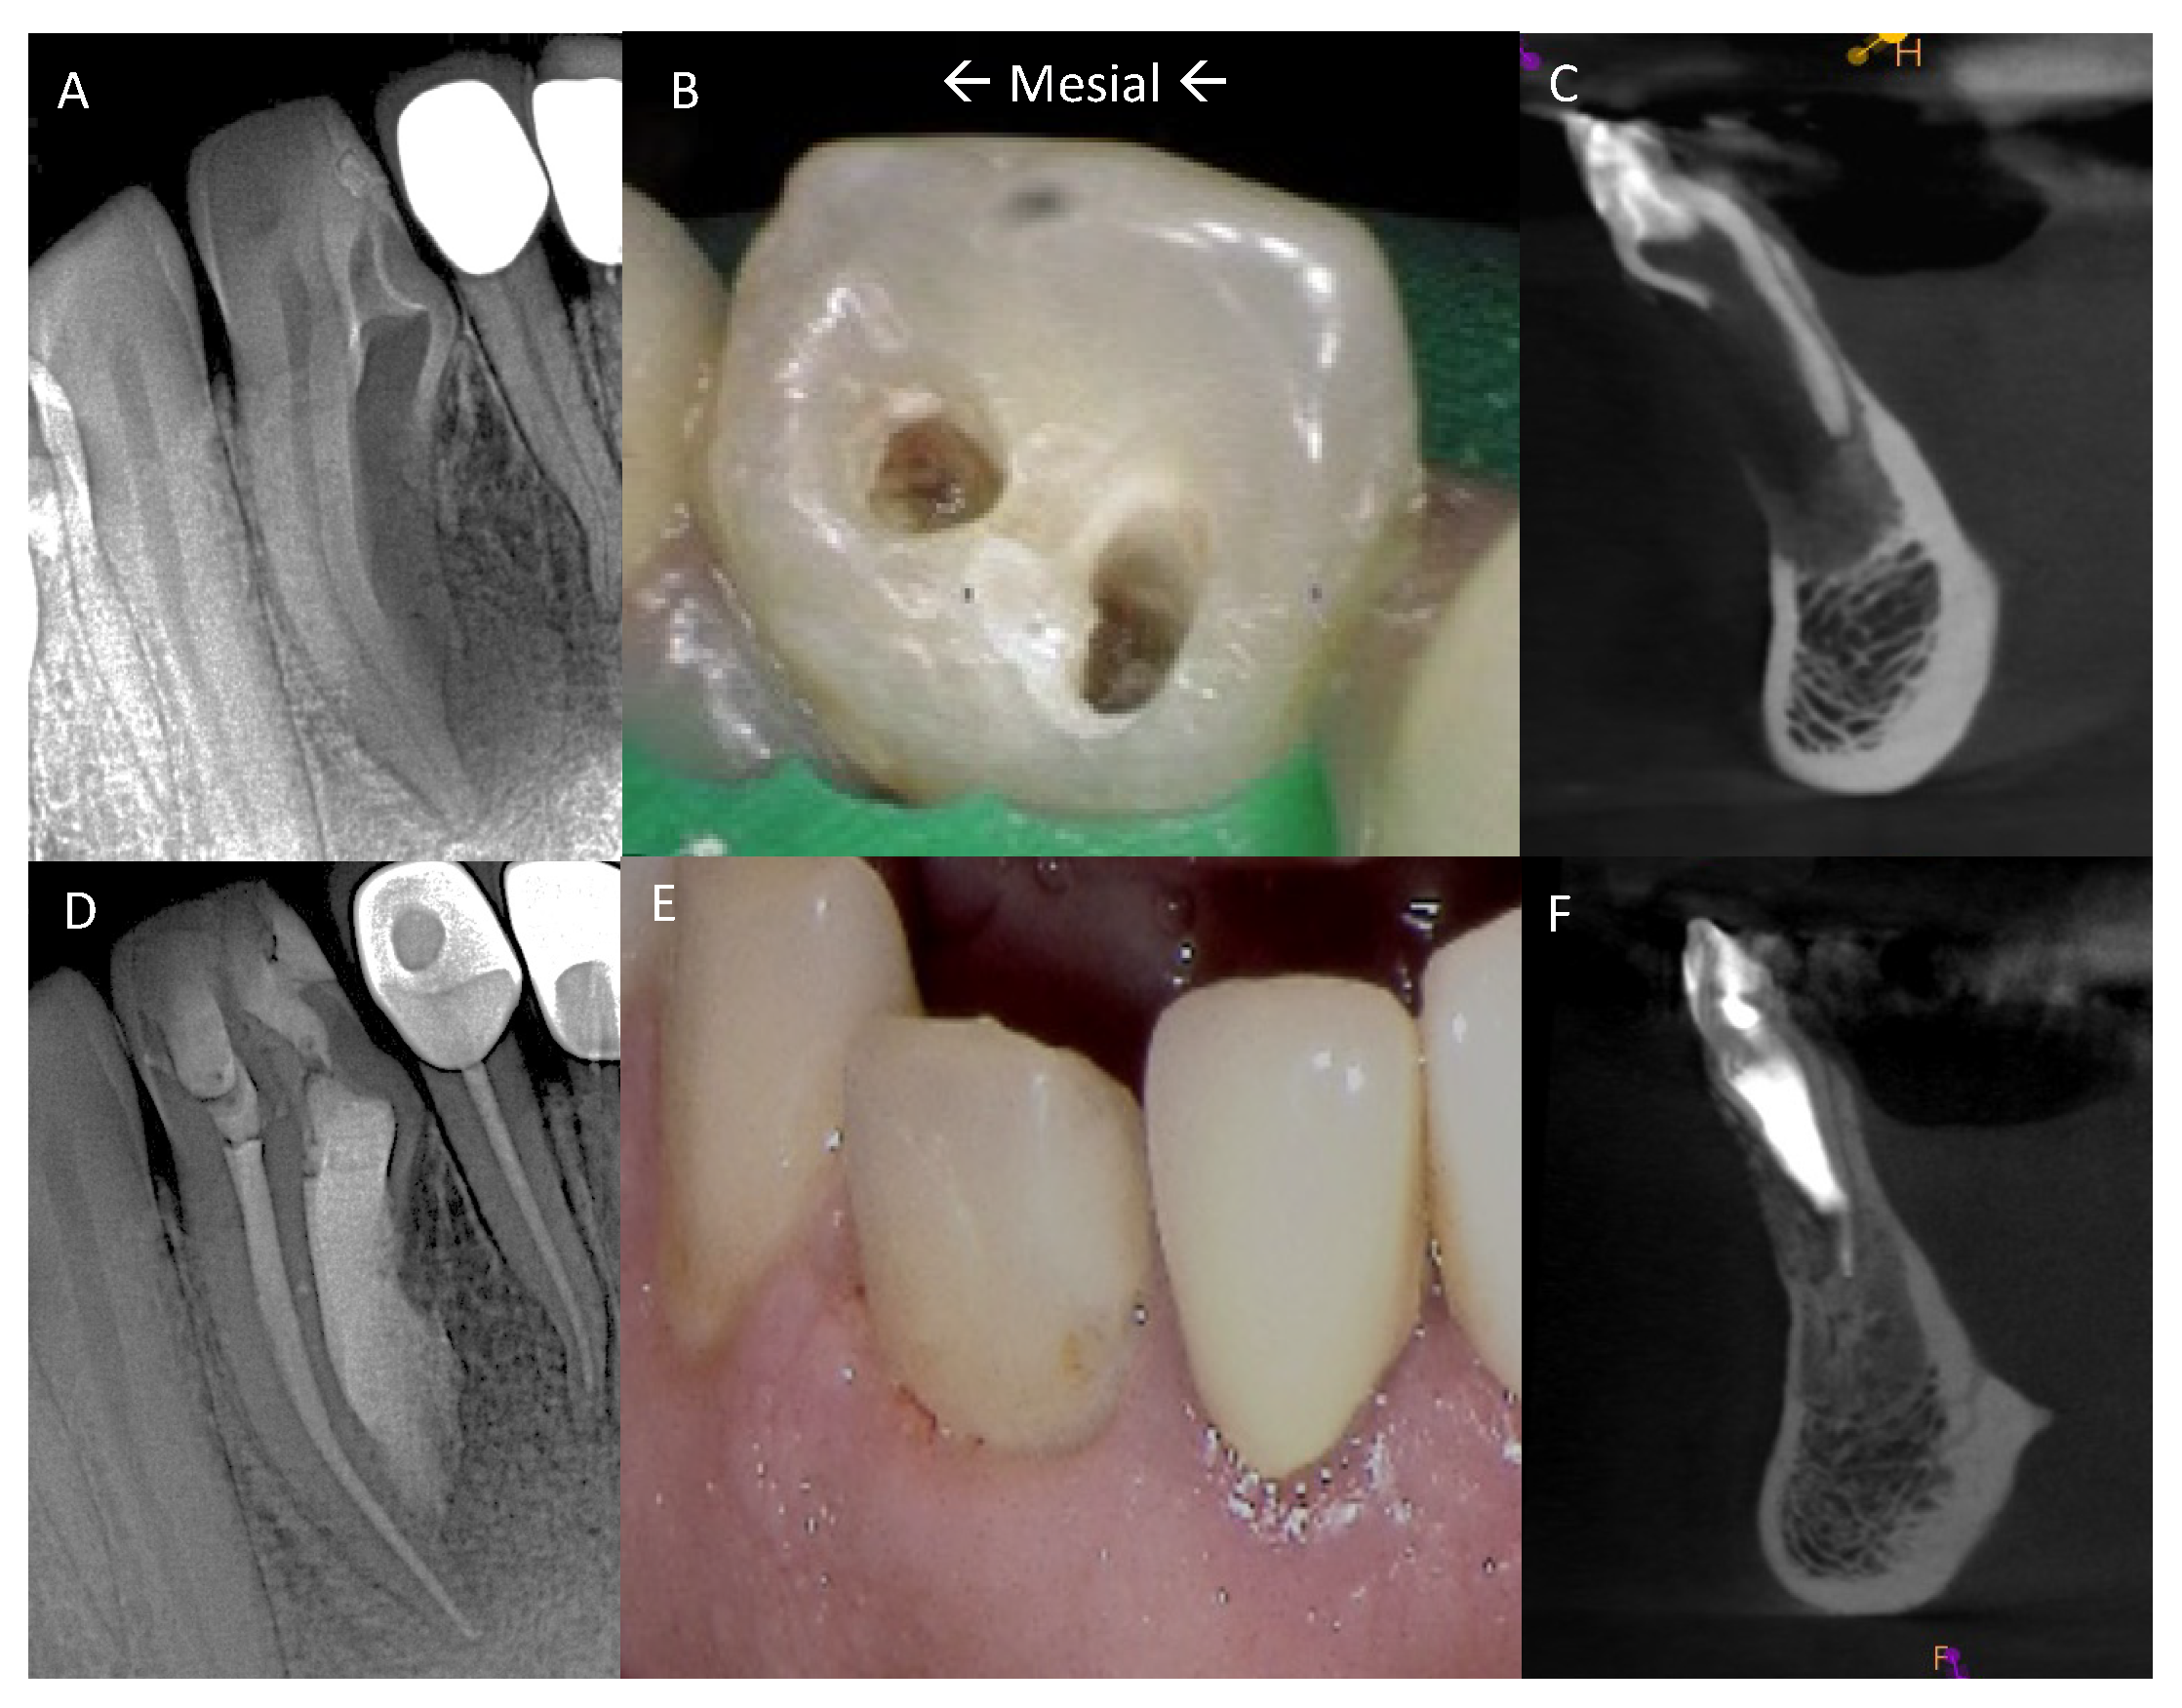

Figure 1. (A) Initial PA taken at endodontic evaluation of tooth #26. (B) Mesial and distal endodontic access cavities. (C) Pretreatment CBCT sagittal section. (D) Final PA after completion of nonsurgical and surgical endodontic treatments and restoration. (E) Photograph of restored tooth #26. (F) Post-treatment CBCT at 6-month follow-up.

Figure 6. (A) CBCT coronal section of tooth #26. (B) CBCT sagittal section. (C) Coronal axial section with both chamber spaces. (D) Axial section apically within the coronal third showing dilated space of DI. (E) Axial section midroot area with lateral DI foramen to the mesial. (F) Axial section in apical third showing the mesiofacial projection and the lingual wing. (G) Apical aspect of DI with lingual wing formation.